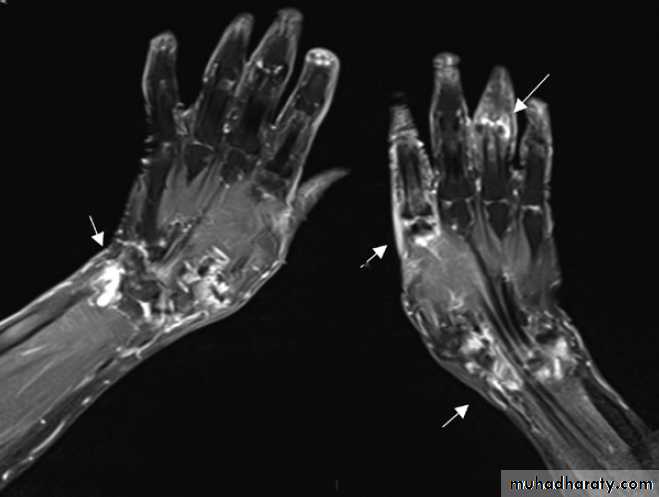

Magnetic resonance imaging

Gives detailed information on anatomy, allowing three-dimensional visualization of bone and soft tissues that cannot be adequately assessed by plain X-rays. The technique is valuable in the assessment and diagnosis of many musculoskeletal diseases . T1-weighted sequences are useful for defining anatomy, whereas T2-weighted sequences are useful for assessing tissue water content, which is often increased in synovitis and other inflammatory disorders . Contrast agents, such as gadolinium, can be administered to increase sensitivity in detecting erosions and synovitis.Conditions detected by magnetic resonance imaging

Magnetic resonance image showing synovitis. Coronal

fat-saturated post-contrast T1-weighted image shows extensiveenhancement consistent with synovitis (white areas, arrowed) in both wrists

and at the second metacarpophalangeal joint and proximal interphalangeal

joints of the right hand.